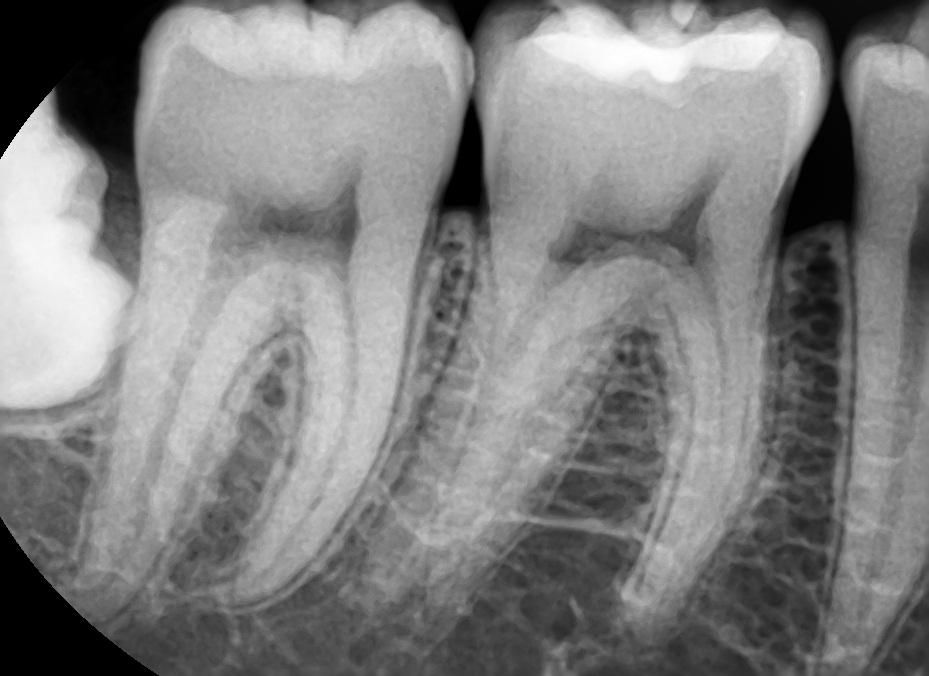

사진속 충치가 다시 번지면 인레이인가요?

사진속 구강상태에서 초기 정지우식이라고합니다. 근데 재광화가풀려 며칠동안 조금이라도 정지우식이 다시 진행되었다면, 진행된지 고작 2주정도 지났다고 쳐도 인레이가 필요한치아가 있나요? 많이 진행되지않고 2주동안 이제막 충치가번지기 시작하는경우, 레진인지 인레이인지 궁금합니다

이정도면 초기상태 충치가 맞고 여기서 좀 더 진행되더라도 인레이까지는 안갈 것 같습니다.

충치가 진행이 되는 것이 치아 사이의 경우에는 보통 레진보다는 인레이로 치료하는 것이 일반적입니다.

충치의 범위가 넓거나 인접면에 충치가 있는 경우에는 보철치료를 하게 됩니다.

범위가 넓지 않다면 인레이 치료를 할수 있지만 범위가 넓다면 크라운 치료가 필요할 수 있습니다.

2주만에 충치가 급격하게 진행될 가능성은 낮으나, 충치가 더 진행되지 않도록 양치를 꼼꼼히 하여 관리하는 것이 필요로 됩니다.